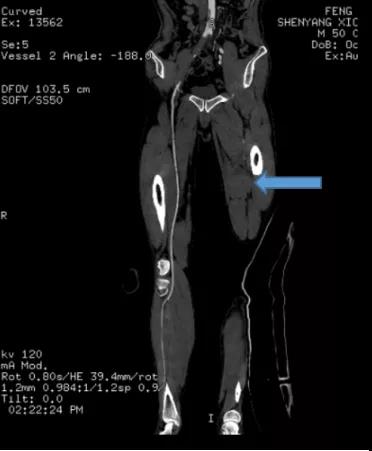

术前CT提示左侧股动脉、腘动脉以及较细血管血流不畅